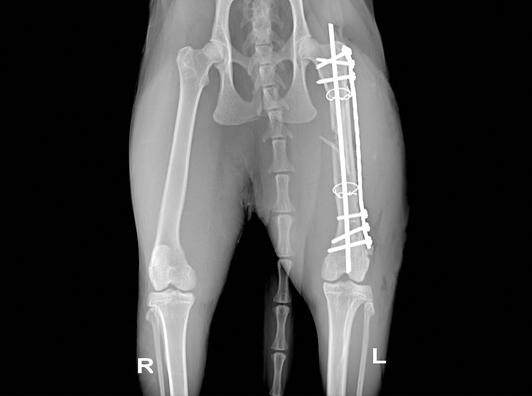

1.基础信息 家猫,年龄1岁,体重2.2kg,雄性,未绝育,从五楼坠落后无法站立和行走,主人带往我医院进行就诊。

2. 临床检查 患猫精神状态萎靡,口色苍白,T:38.3℃,P:86次/分,R:32次/分,呼吸急促,卧地不起,右前肢及双后肢解剖姿势异常,轻微牵引疼痛感明显,可闻及明显骨摩擦音。

4. 初步诊断 综合以上各项检查,初步诊断为右肱骨远端粉碎性骨折合并双侧腓骨远端骨折、双侧距骨粉碎性骨折。

5. 治疗 本病例胸腹部X线片检查未见明显异常,但鉴于患猫体况较差,术前3天给予输液预防继发感染、增加营养等,待患猫体况好转后,实施内固定手术。 丙泊酚诱导麻醉、异氟烷维持麻醉后,患肢备皮消毒。